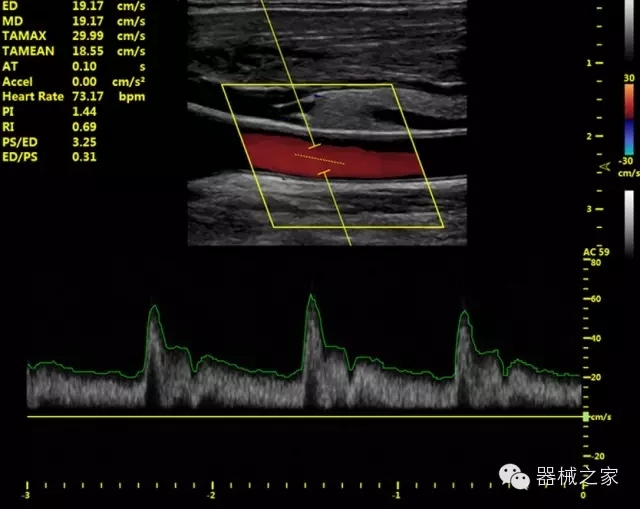

臨床圖片賞析

產(chǎn)品特點(diǎn)

優(yōu)異的成像技術(shù)

·亞陣元技術(shù):獨(dú)有的亞陣元技術(shù),對(duì)獨(dú)立晶片做二次切割,減少旁瓣偽像,增加臨床診斷的準(zhǔn)確性;

·μ-Scan微米成像技術(shù):開(kāi)立獨(dú)有的μ-Scan技術(shù),還原出真實(shí)細(xì)膩、層次對(duì)比優(yōu)異的二維圖像;

·倒相諧波成像技術(shù):倒相諧波技術(shù)在去除基波信號(hào)的基礎(chǔ)上獲取兩倍二次諧波信號(hào),提高組織圖像的對(duì)比分辨力;

·智能微血流成像技術(shù):智能微血流捕捉技術(shù)可以提取出隱藏在背景噪聲中的弱血流信號(hào),大大提高低速血流的敏感性;

全面的臨床解決方案

超聲科常規(guī)領(lǐng)域應(yīng)用

·移植S40高端臺(tái)式彩超高端平臺(tái)技術(shù),滿足超聲科腹部、淺表、婦產(chǎn)科、心血管、肌骨等應(yīng)用,提供超聲科完美解決方案;

·實(shí)時(shí)的彈性成像技術(shù):提高了小器管(乳腺,甲狀腺、淺表軟組織腫瘤等)疾病鑒別診斷;

·IMT血管內(nèi)中膜自動(dòng)測(cè)量:為血管性疾病評(píng)估提供了有效的評(píng)估手段;